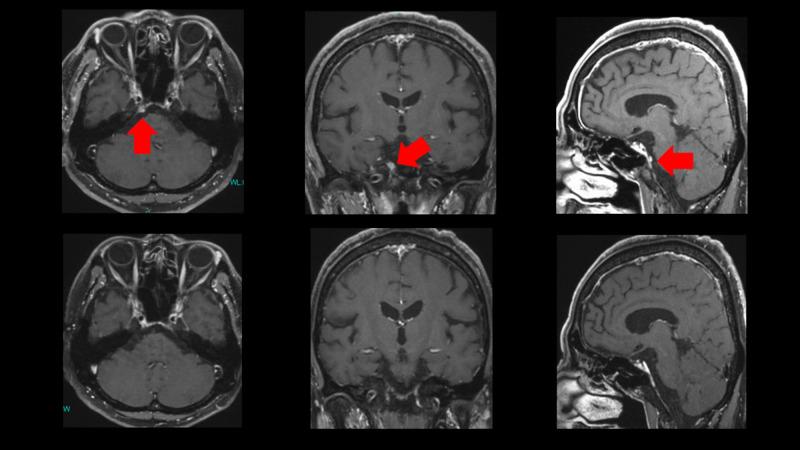

Skull base petroclival metastases cause diplopia due to abducens nerve palsy. Diplopia is visually disabling, and skull base metastasis is extremely difficult to treat even with microscopic surgery. However, stereotactic radiotherapy with CyberKnife (Accuray Incorporated, Sunnyvale, California) has been very successful in 10 cases. As the abducens nerve runs through Dorello's canal in the skull base, the radiation dose and fraction were adjusted to avoid damage to the nerve. Since these metastases are not located inside the brain but in the skull base, contrast magnetic resonance imaging (MRI) combined with fluorodeoxyglucose-positron emission tomography (FDG-PET) was essential to detect the cancers.

颅底岩斜区转移瘤可因展神经麻痹导致复视。复视会导致视力障碍,即便采用显微手术,颅底转移瘤也极难治疗。然而,使用射波刀(Accuray Incorporated,加利福尼亚州桑尼维尔)进行立体定向放射治疗已在10例患者中取得了非常成功的效果。由于展神经穿过颅底的Dorello管,因此需调整放射剂量和分割方式以避免损伤该神经。由于这些转移瘤并非位于脑内而是在颅底,因此对比磁共振成像(MRI)联合氟脱氧葡萄糖正电子发射断层扫描(FDG-PET)对于检测癌症至关重要。